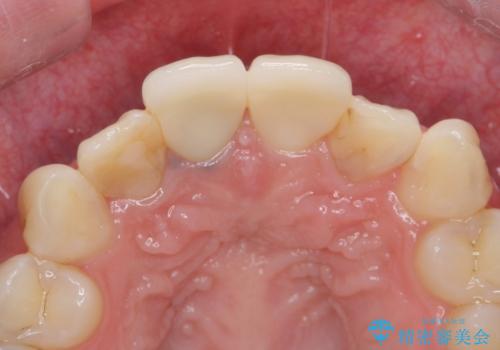

- ジルコニアクラウンスタンダード・仮歯 13.2万円×2費用は治療当時の料金となります

色のバランスもよく、適合も良い被せ物が入りました。

根管治療をした後、樹脂で埋めるだけで治療を終えてしまうと歯質と樹脂の隙間から細菌が入り込み、う蝕や根の感染の再発に繋がります。

適合の良い被せ物を入れることで再発リスクが低くなります。